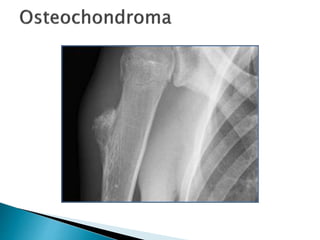

 Osteochondroma isa bony protrusion covered by a cartilaginous cap.  Growth of the osteochondroma takes place in the cap, corresponding with normal enchondral growth at the growth plates.  Accordingly, growth of osteochondromas is allowed until a patient reaches adulthood and the physeal plates are closed.  Growth of osteochondromas at adult ages, which is characterized by a thick cartilaginous cap (high SI on T2WI) should raise the suspicion of progression to a peripheral chondrosarcoma